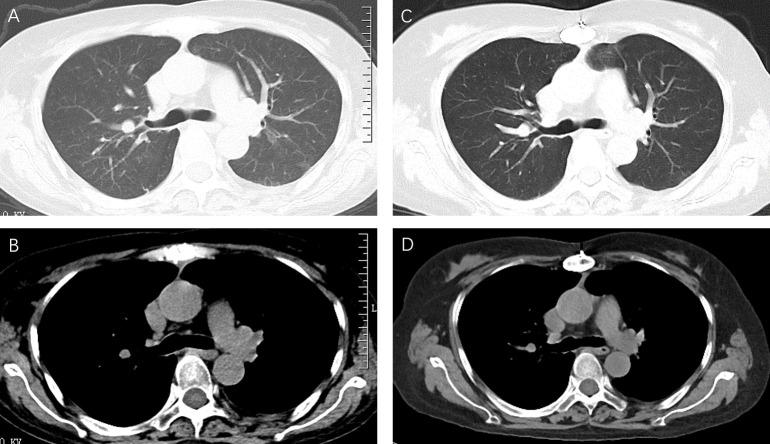

The aim of this study is to report an isolated pleural cryptococcosis with pleural effusion as the only manifestation, confirmed by pleural biopsy in a patient with thymoma combined with myasthenia gravis, who developed pleural effusion of unknown origin after long-term glucocorticoids and tacrolimus therapy.

A biopsy specimen of the right pleura revealed numerous yeast-like organisms surrounded by mucous capsules and neoformans was detected by mNGS with a species-specific read number (SSRN) of 4, confirming the diagnosis of pleural cryptococcosis. Pleural effusion was eliminated with amphotericin B and fluconazole, and healthy status was maintained at the time of review 1 year later.

Cryptococcosis, manifested by simple pleural effusion, is extremely rare, but when repeated pleural effusion occurs in immunocompromised patients or in patients with malignant tumors, the possibility of cryptococcosis should be treated with high vigilance and pleural biopsy is recommended if necessary in order to confirm the diagnosis.